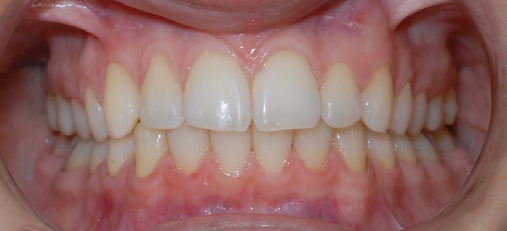

Class I Non-Extraction |